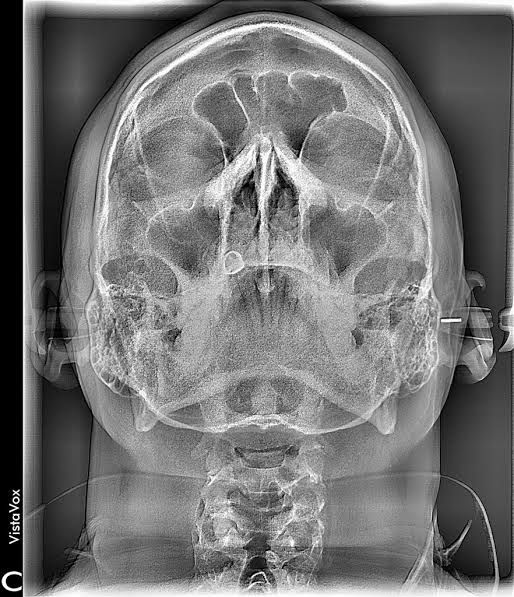

Radiografía posteroanterior (PA) con trazado

Permite la evaluación precisa de la simetría facial, la relación entre las estructuras óseas y la posición de los arcos dentales.

Radiografía postero anterior de cráneo

Técnica radiográfica utilizada para evaluar asimetrías, traumatismos y patologías craneofaciales.